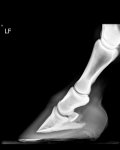

Hello, I had some x-rays done of my 3yr warmblood as suggested, which confirmed that he has a club foot - not entirely sure how or when it developed or if it was from a foal or later.

The vet has suggested that a check ligament desmotomy might help to correct the angle. As you can see the ligament is short on the xray, I hope this may help his long term health.

Said x-rays of front feet: